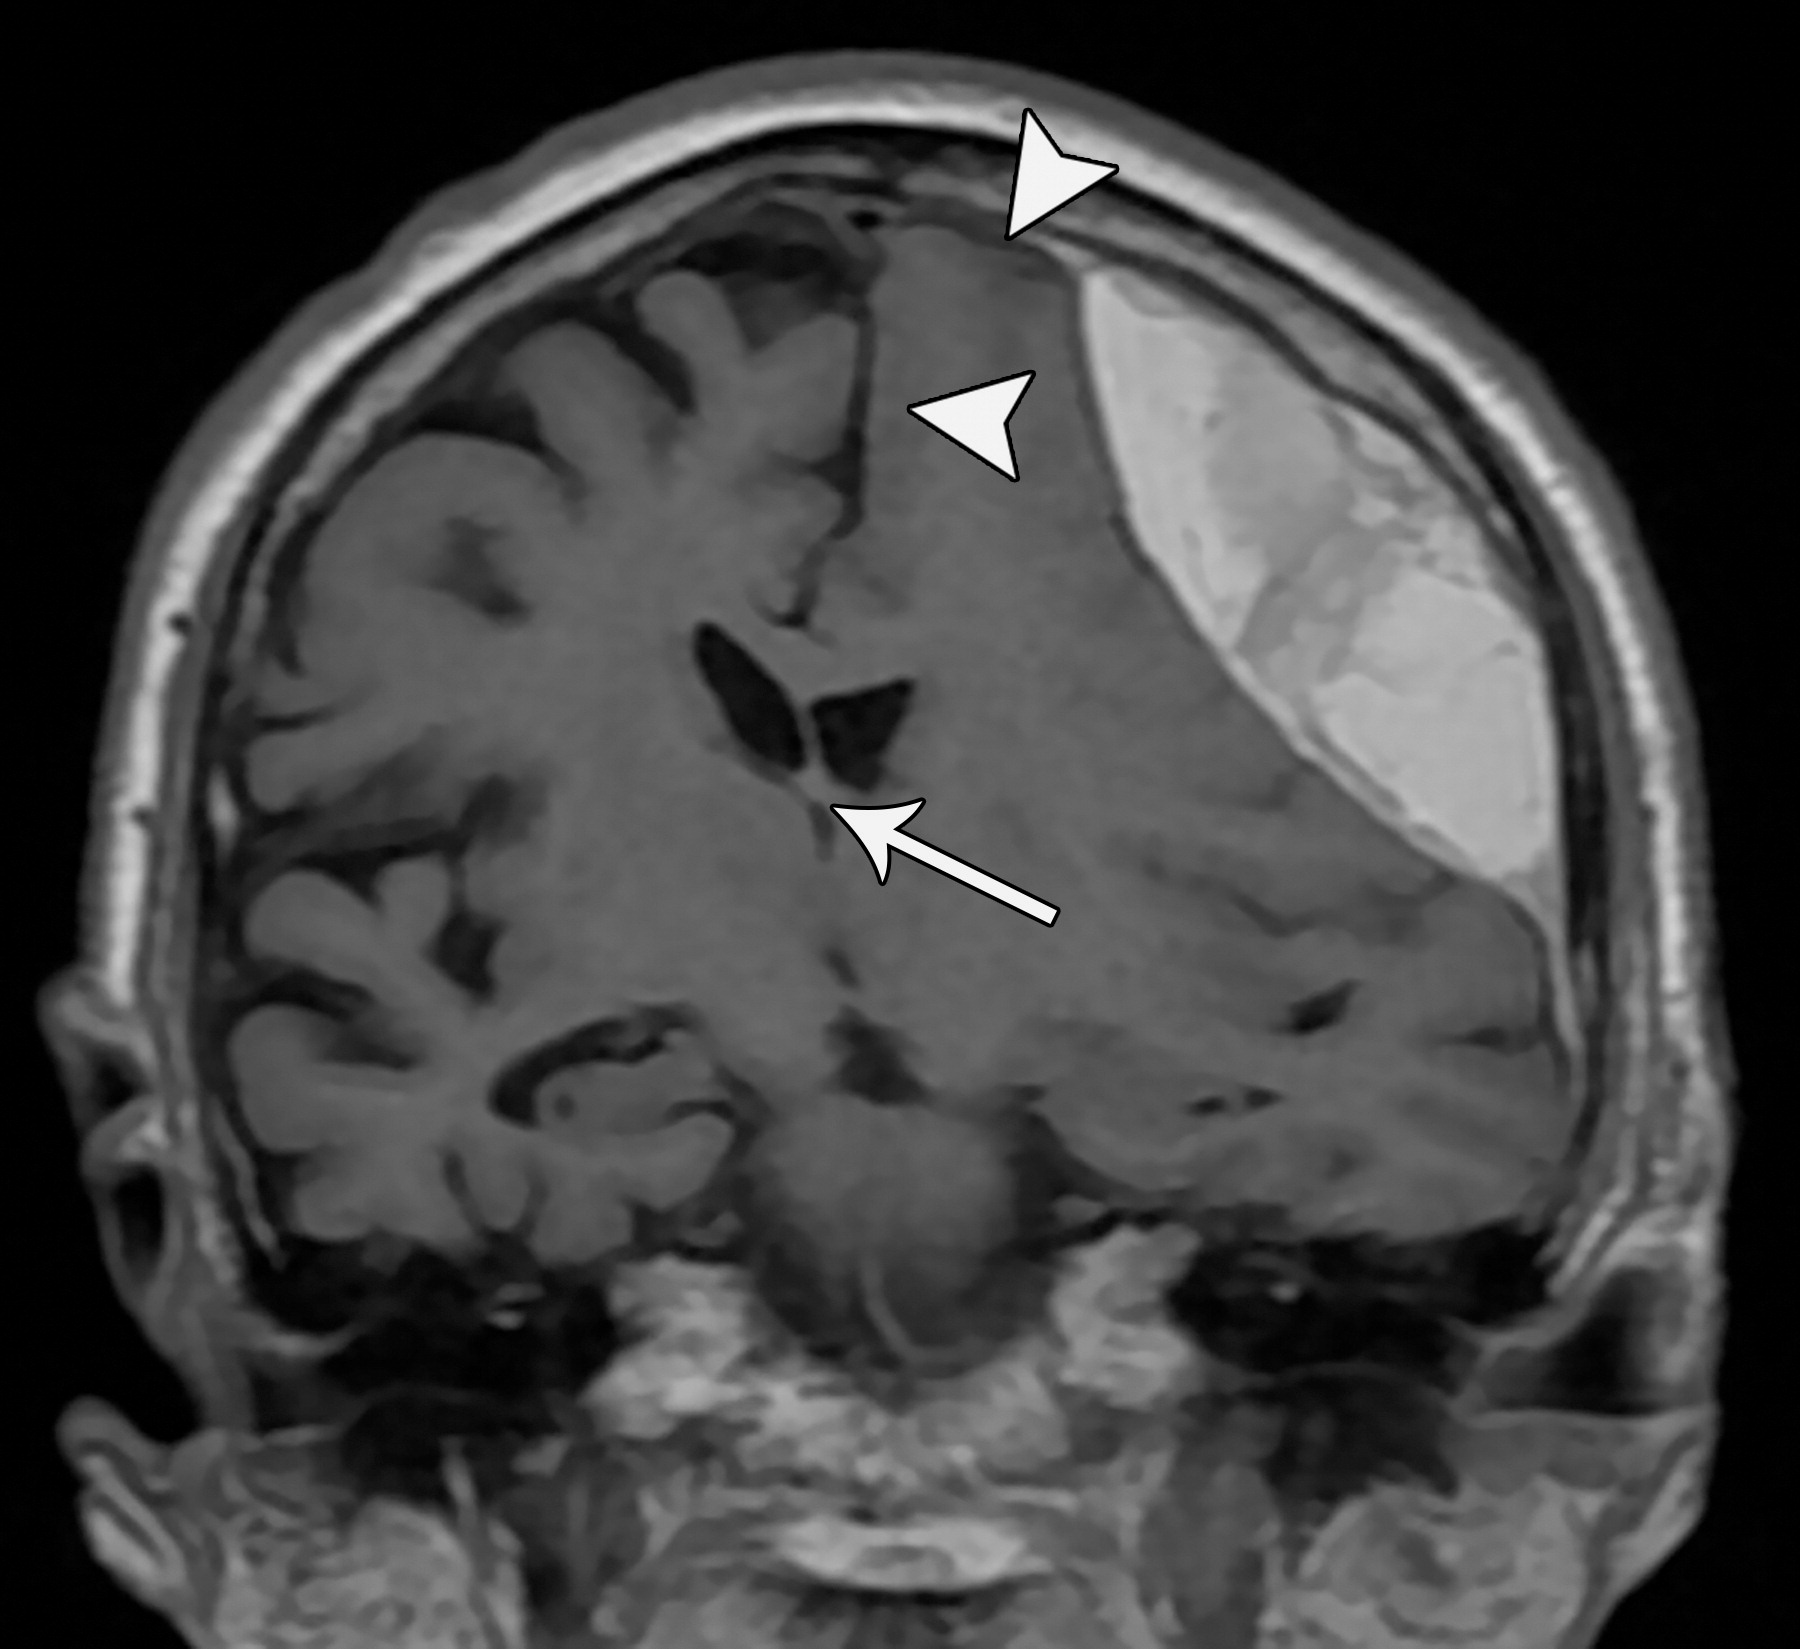

e10b81f69aecfde7ed5f5612478dbcdc.jpeg

33岁男性,生殖细胞肿瘤脑转移患者的大脑镰下疝:冠状增强CT示大脑穹隆游离缘下方的扣带回从左向右疝入(白色弯箭头),并伴同侧胼胝体(*)的下侧移位,注意同侧脑室受压和对侧脑室的扩张(白色箭头)。